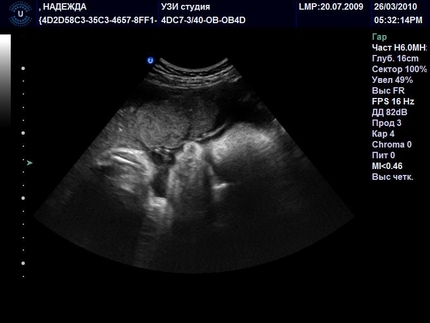

УЗД на 39 тижні вагітності (фото)